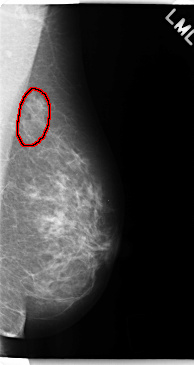

ics_version 1.0 filename C-0241-1 DATE_OF_STUDY 22 2 1995 PATIENT_AGE 63 FILM FILM_TYPE REGULAR DENSITY 2 DATE_DIGITIZED 28 4 1998 DIGITIZER LUMISYS LASER SEQUENCE LEFT_CC LINES 4752 PIXELS_PER_LINE 2624 BITS_PER_PIXEL 12 RESOLUTION 50 OVERLAY LEFT_MLO LINES 4744 PIXELS_PER_LINE 2512 BITS_PER_PIXEL 12 RESOLUTION 50 OVERLAY RIGHT_CC LINES 4712 PIXELS_PER_LINE 2656 BITS_PER_PIXEL 12 RESOLUTION 50 NON_OVERLAY RIGHT_MLO LINES 4728 PIXELS_PER_LINE 2656 BITS_PER_PIXEL 12 RESOLUTION 50 NON_OVERLAY |

FILE: C_0241_1.LEFT_MLO.OVERLAY TOTAL_ABNORMALITIES 1 ABNORMALITY 1 LESION_TYPE MASS SHAPE IRREGULAR MARGINS ILL_DEFINED ASSESSMENT 4 SUBTLETY 5 PATHOLOGY BENIGN TOTAL_OUTLINES 1 BOUNDARY |